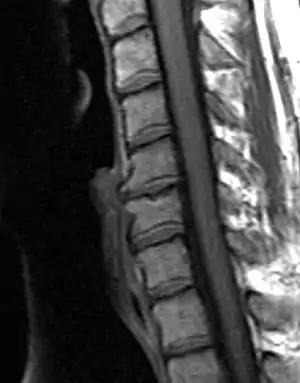

| Degenerated disc between C5 and C6 (vertebra at the top of the picture is C2), with osteophytes anteriorly (to the left) on the lower portion of the C5 and upper portion of the C6 vertebral body. | |